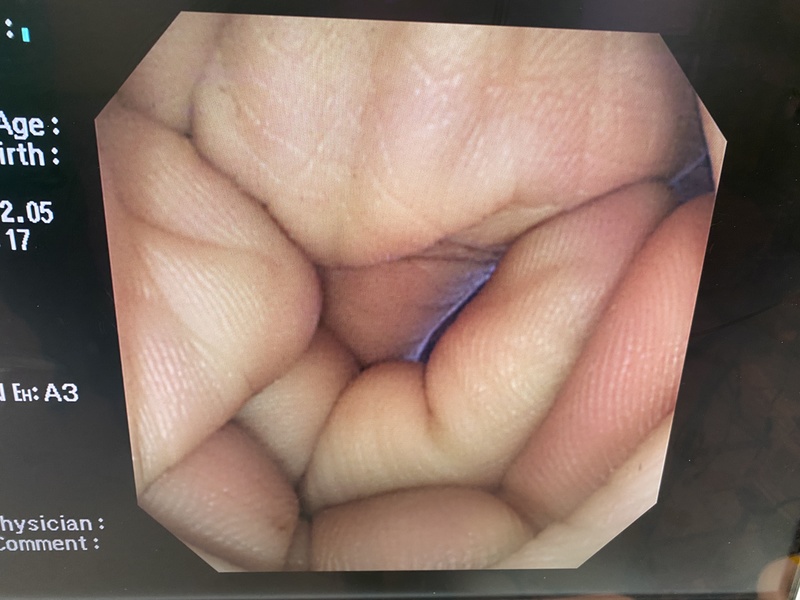

- detail Video Colonoscope / 16923 / CF-240I